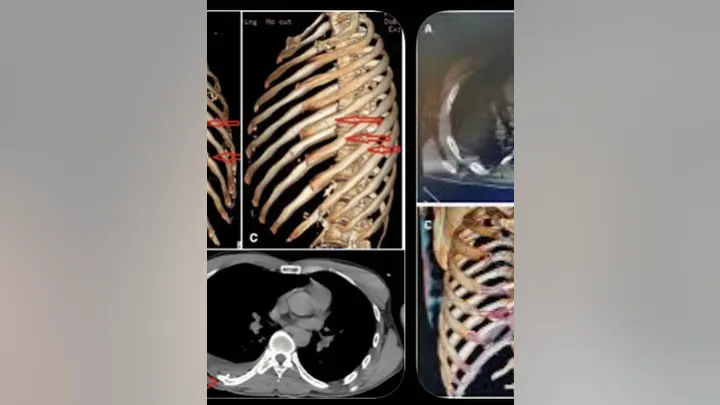

“It was a major wreck, but fortunately it’s bones that’ll heal, no internal damage or anything like that,” Harrison added. “He’s just in a lot of pain. If you’ve ever broke a rib, you know what it’s like. He broke 11. He’s got 11 fractures of his ribs.”

On Jan. 26, Corey revealed he had been injured in a solo motorcycle crash, and he showed off his injuries in a carousel of images on Instagram.

“Pretty messed up but I’m good crash bars are awesome 3 nights in the hospital 11 breaks in my rib cage,” he wrote. “Will do an episode on @theCoreyHarrisonshow.

Corey broke 11 ribs in the crash.  (Corey Harrison Instagram )